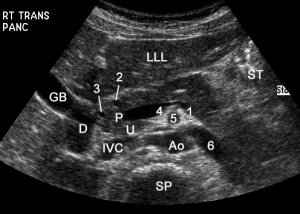

Патологія на УЗД

Діагностика гастродуоденіту включає:

- здача лабораторних аналізів (сеча і кров), що вказують на можливий розвиток запального процесу

- визначення підвищення рівня жовчі, що впливає на майбутні методи лікування

- УЗД (ультразвукове обстеження шлунка і 12-палої кишки), допомагає виявити присутність виразкових утворень

- Рентген (рентгенологічне дослідження), що виконується з контрастним речовиною, на тлі якого проступають виразки і рубці

- Фіброезофагогастродуоденоскопія: в порожнину шлунка через ротову порожнину вводиться тоненька трубка з мініатюрною камерою доповненої освітленням (дає точну картину про стан слизової на стінках органу) для дослідження та біопсії

При необхідності можуть застосовуватися додаткові методи діагностики. Тільки після визначення загальної клінічної картини лікар встановлює діагноз, і на підставі всіх особливостей хвороби та організму визначає схему терапії.